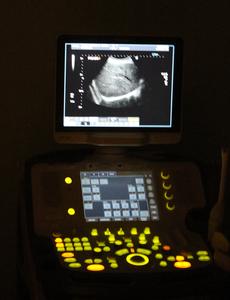

Para detectar as doenças com antecedência, a tradicional ecografia ainda é a mais utilizada. Porém, o exame não-invasivo recebe inovações tecnológicas constantes. Se antigamente o exame era utilizado apenas para visualizar o tamanho e posição do bebê, atualmente é possível realizar um mapeamento cromossômico e verificar se há riscos de síndromes genéticas e malformações com bastante antecedência.

- A ecografia não oferece riscos para a mãe ou o feto, e com este exame simples, é possível saber sobre diversas alterações na formação do bebê. A técnica permite o diagnóstico e tratamento de fetos ainda intra-útero, e se necessário, a realização de tratamento logo após o parto. Hoje não precisamos mais esperar o nascimento do bebê para saber sobre certas complicações e malformações - explica a médica , especialista em medicina fetal da Mamorad, Alice Calone.

Também através da ecografia é possível saber até se o bebê sofre de anemia, casos que podem acontecer em algumas gestações em que há incompatibilidade entre o sangue materno e fetal. Utilizando o recurso da Dopplerfluxometria, é viável verificar o fluxo do sangue na cabecinha do bebê, evitando exames invasivos. Após realizar a medição, é possível verificar se a doença existe, e avaliar a necessidade de realizar a transfusão sanguínea ainda intra-útero, ou apenas administrar a gestação com maior atenção.